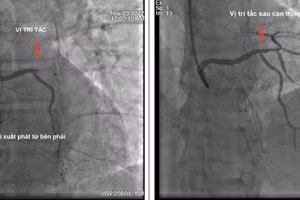

Người đàn ông phát hiện dị tật bẩm sinh hiếm gặp sau cơn nhồi máu cơ tim 22/12/2022 14:17 GD&TĐ - Bệnh viện Quân y 103 vừa cấp cứu, điều trị thành công bệnh nhân nhồi máu cơ tim cấp có bất thường giải phẫu động mạch vành rất hiếm gặp.